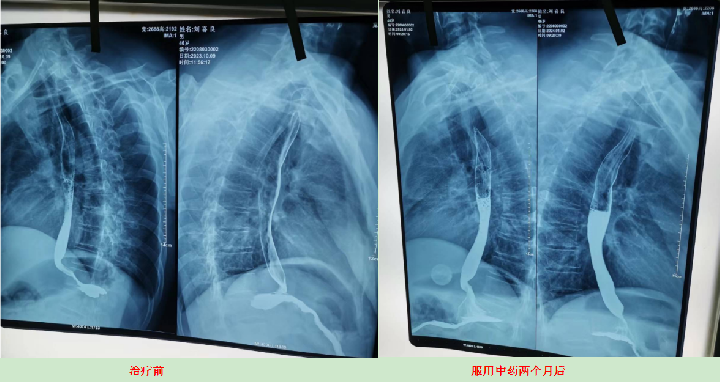

2023年10月9日CT影响报告诊断查出食管壁增厚,管腔狭窄,食管癌。找到陈海林老师使用中医药两个月治疗后CT显示食管各段顺利通过,食管恶性肿瘤治疗后改变。

上图是服用两个月中药的前后对比图

上图是服用两个月中药后检查报告对比图